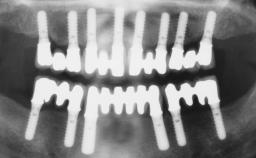

Iliac-Crest Block for Vertical and Horizontal Space Filling in the Anterior Maxilla

Waldemar Daudt Polido, Joao Emilio Roehe Neto

A 31-year-old man presented to our clinic 30 days after a motor vehicle accident in which he had suffered a dentoalveolar fracture in the anterior maxilla, including avulsion of teeth 12 and 11 and luxation of tooth 21. He was first treated on the night of the accident in a small city hospital with no oral and maxillofacial surgeon on the staff. A wired retention had been applied and the teeth repositioned to the best of the clinicians’ abilities. When he first presented to our care, the patient showed extrusion of teeth 12 and 11 associated with gingival recession due to bone loss in the anterior maxilla, and the stainless steel wires were still present.

# of Implants 3

Type of Implants One-Piece|Reduced-Diameter

Bone Augmentation Horizontal|Staged|Vertical

Augmentation Materials Autogenous chips|Autogenous block(s)

Prosthesis Type FDP